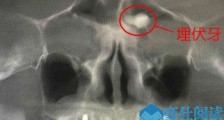

- 男子额头长一颗牙 这竟是他得怪病的原因难以置信【热点】

- 按照常识,只有嘴巴里才有牙齿,但是却有一男子额头长一颗牙了,想必很多人对此状况也是从未见过吧,所以很难相信牙齿竟然可以长在额头上的,可这却真实的发生的了,该男子也因为这颗牙...

- 额头竟长了一颗牙怎么回事 额头藏牙原因揭秘真相令人惊【热点】

- 要是有人跟你说,额头上长有牙,你信吗?近日,在深圳某医院里,一名中年男子的额头,竟然长了一颗牙!在经过CBCT拍摄发现,该名男子额头“藏”有牙,这还真是闻所未闻的世间“奇事”啊!下面,就...